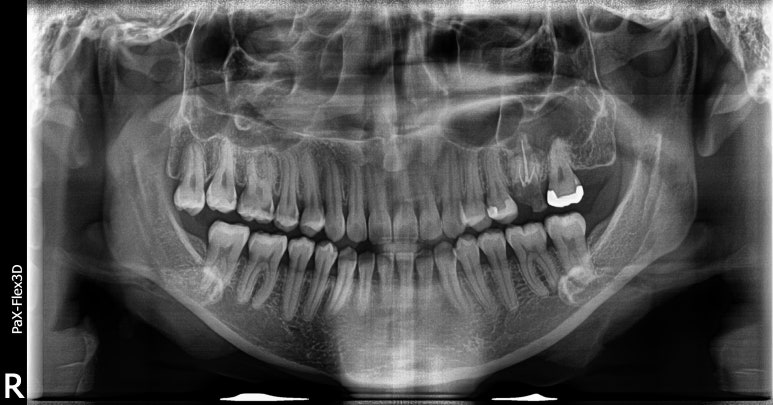

20대임플란트 실제 사례

28세 남성

(전) 2022-07-07 (후) 2022-09-02